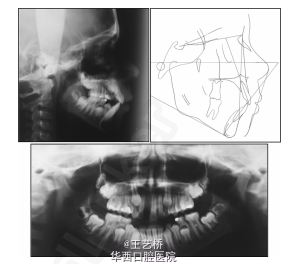

在切牙牙根发育阶段出现外伤导致上切牙缺失比较常见。这种情况下种植等修复存在一定的局限性(特别是创伤骨质)。患者10岁,2年前外伤导致11牙缺失,牙列拥挤。修复方法有两种,一种是拔除21牙(21牙存在牙髓炎症状),两侧侧切牙近中移动关闭间隙,下颌拔除前磨牙进行正畸。此方法无法建立I类关系,且前牙区美观不佳,甚至有可能出现骨质吸收。因而决定采用自体45牙移植,既能够获得满意的美观,也能够促进上颌骨垂直生长。